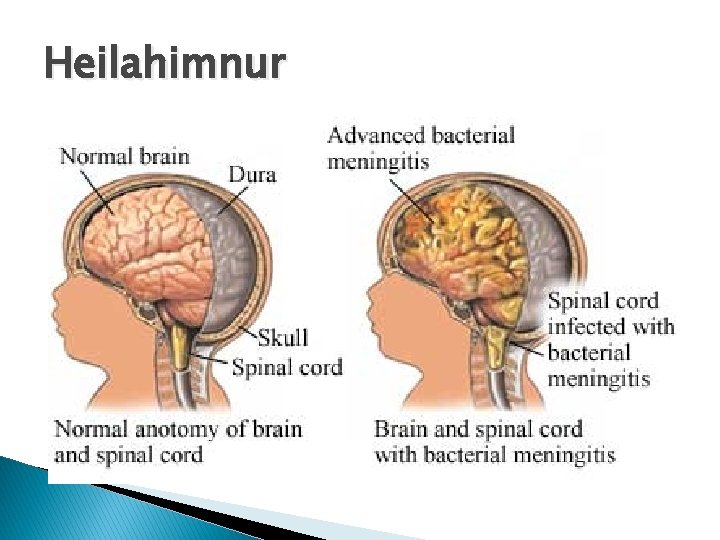

Heilahimnur � Heilahimnurnar (meninges) eru þrjár ◦ Yst er dura mater ◦ Í miðjunni er arachnoid mater �Undir henni er subarachnoid space þar sem margar stórar æðar liggja og heila- og mænuvökvinn er ◦ Pia mater er alveg límd við heilann og er örþunn ◦ Heilahimnubólga (meningitis) verður vegna bakteríu - eða vírussýkinga (örfá sinn vegna lyfja) ◦ Bakterían sem veldur hvað mestu tjórni nefnist Neisseria meningitidis. Þrátt fyrir sýklalyfjameðferð deyja um 10% og margir skaddast varanlega